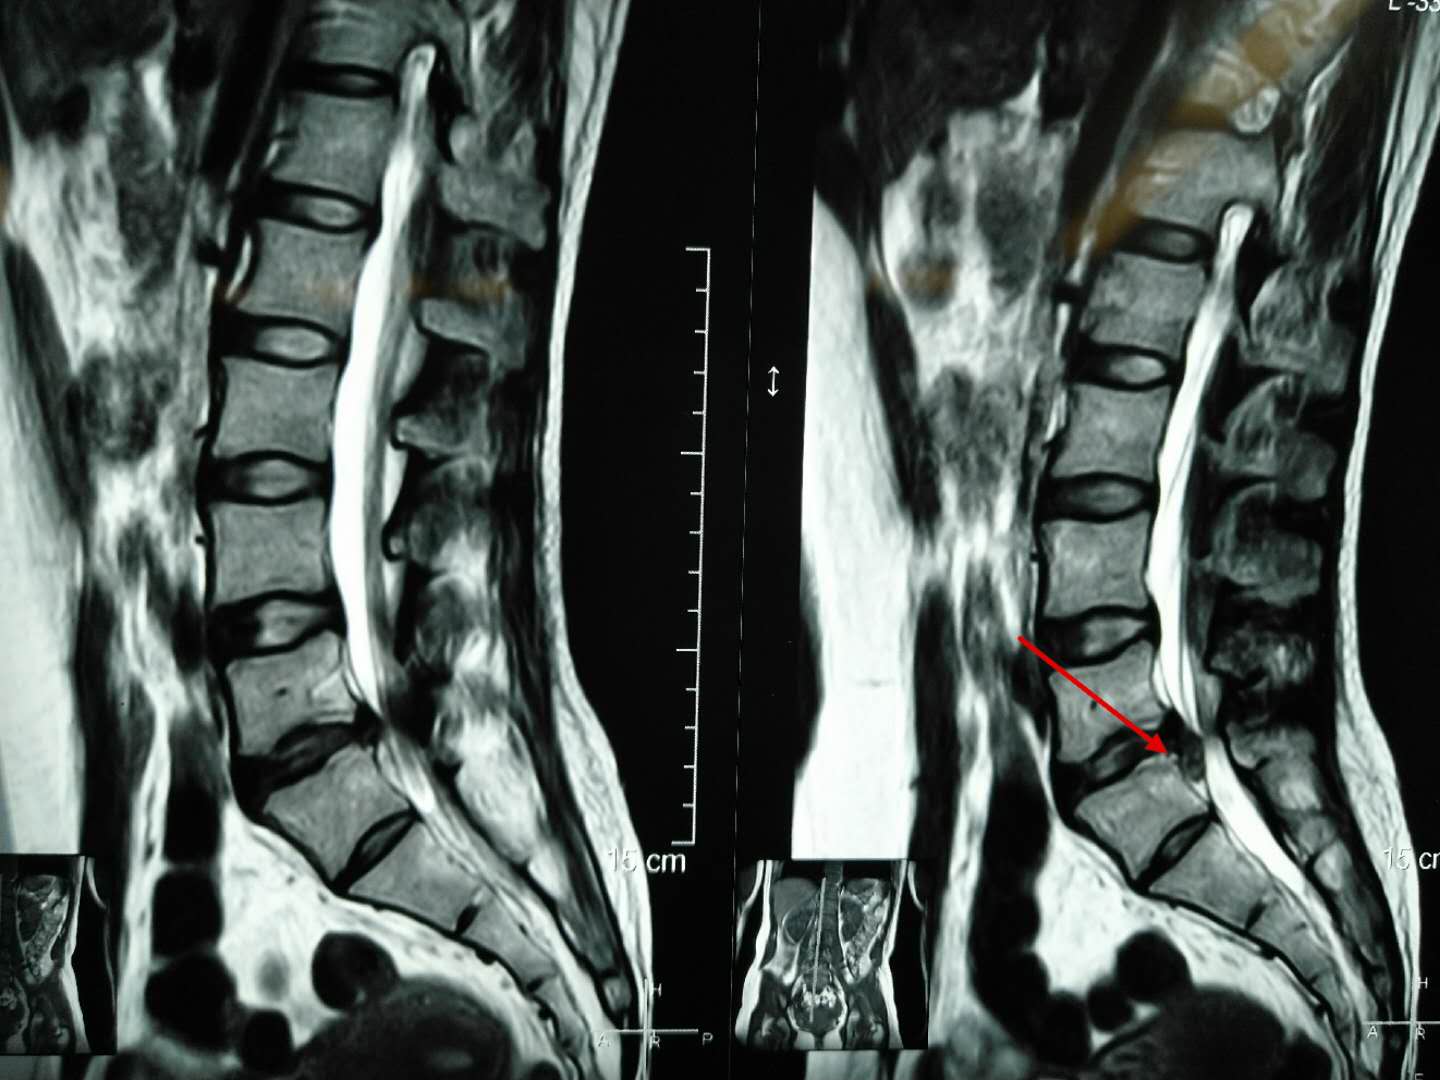

这位患者饱受腰椎间盘突出折磨之苦,平时只能爬着好受一些,只要一翻身平躺或者下地行走右腿麻疼的厉害,晚上基本就得靠止疼药才能睡几个小时,然后就被疼醒。

从术前的腰椎磁共振我们可以看到腰椎向下脱垂游离的巨大间盘突出,压迫右侧神经根,我们给她做了后路脊柱内镜下腰椎间盘摘除术。